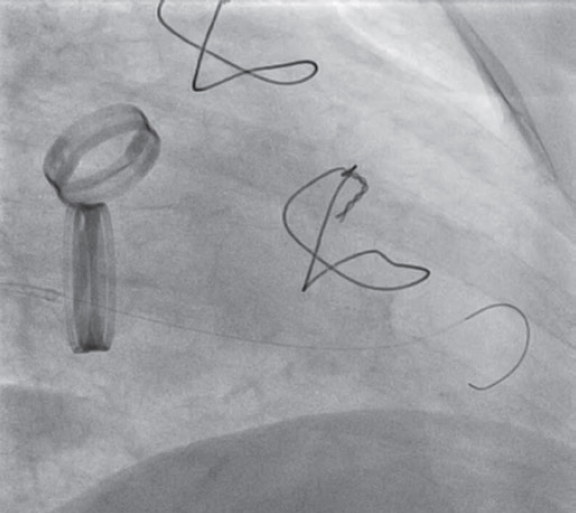

Debido a que el disco estaba bloqueado en una posición casi completamente cerrada (vídeo 1 del material adicional), optamos por un enfoque menos agresivo que el descrito por Jabbour et al.1 y en vez de manipular el disco con el catéter guía decidimos utilizar un catéter balón. Para ello, por el catéter guía se avanzó una guía de 0,014 pulgadas Balance Middleweight hacia las cavidades izquierdas. Aunque el alambre guía tendió a avanzar hacia al ventrículo izquierdo a través del espacio que dejaba el disco móvil al abrirse, después de varios intentos se pudo dirigir a través del pequeño espacio entre el disco bloqueado y el anillo protésico (figura 1) (vídeo 2 del material adicional). Con el extremo de la guía apoyado en el ápex, se avanzó suavemente un catéter balón no distensible Medtronic NC Euphora 5,0 × 15 mm que se infló varias veces a nivel del anillo mitral hasta que el disco bloqueado se liberó por completo (figura 2) (vídeos 3 y 4 del material adicional). La ecocardiografía transesofágica realizada después del procedimiento mostró la normalización de la función de la válvula protésica con un gradiente medio de 5 mmHg y un movimiento adecuado de ambos discos (figura 3). La paciente fue extubada inmediatamente después de la intervención sin complicaciones y no hubo eventos tromboembólicos ni hemorrágicos posteriores. Fue dada de alta 2 días después del procedimiento, con anticoagulantes orales y ácido acetilsalicílico. Un estudio sistemático descartó alteraciones de la coagulación y la paciente permanecía asintomática a los 12 meses de seguimiento.

Figura 1. Paso de la guía al ventrículo izquierdo.